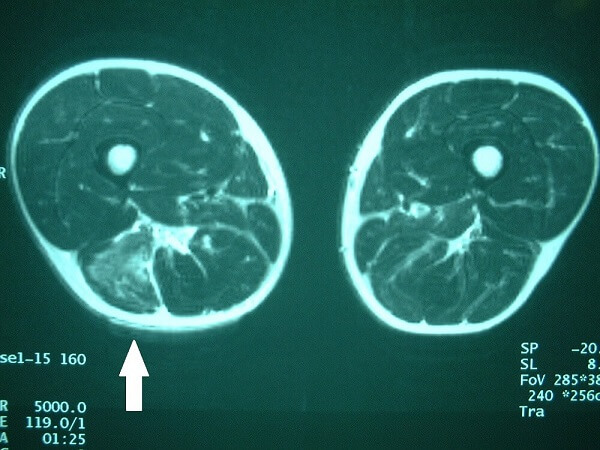

MRIは受傷初期から、血腫範囲や受傷部位の確認が可能です。超音波でも血腫の確認はできますが、数日経過したほうがわかりやすくなります。

写真2 矢印は右大腿ハムストリングス肉ばなれのMRI